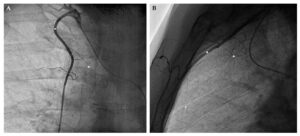

- سونوگرافی، که از امواج صوتی برای ایجاد تصاویری از وریدها استفاده می کند.

- ونوگرافی، که شامل تزریق یک رنگ مخصوص به رگ ها و گرفتن عکس اشعه ایکس برای مشاهده ی جریان خون است.